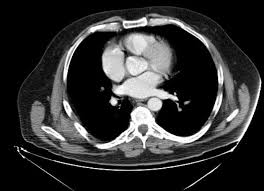

Pin By Varsha Kunwar Gautam On Excalibur Healthcare S Imaging Teleradiology Pins Radiology Imaging Radiology Ct Scan